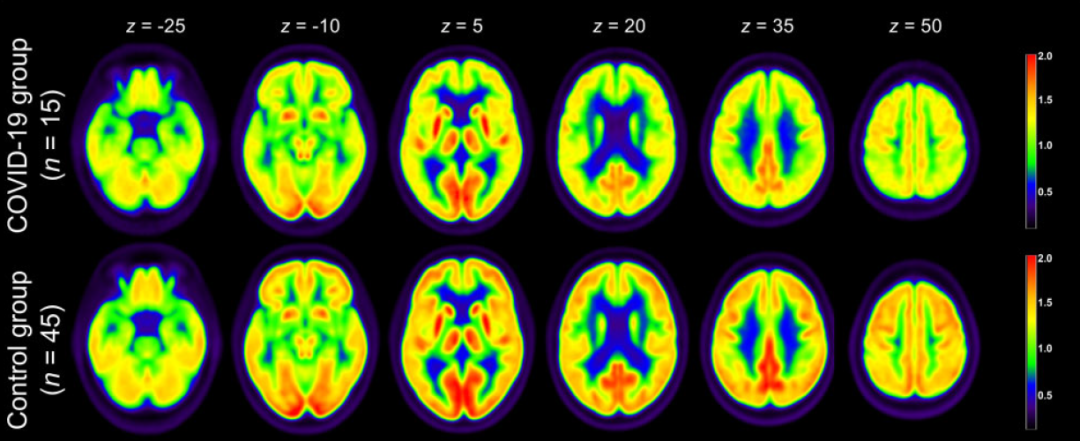

被新冠病毒感染后,部分患者的首发症状表现为嗅觉、味觉减退或丧失等。这些感觉器官功能的改变其实反映的是中枢神经系统(脑)结构或者生理的变化。脑部成像可以清晰地记录到这种变化,但是通过医学影像学手段直接观测新冠肺炎患者中枢神经系统变化的报道很少。德国弗莱堡大学医学中心教授 Jonas A. Hosp 团队通过对15名处于亚急性期且嗅觉和味觉出现异常的新冠肺炎患者的脑部进行PET(正电子发射型计算机断层显像,可通过检测人体的代谢水平判断疾病的发生发展)成像分析后发现,有10名患者的额顶叶位置出现代谢水平下降的现象 [1]。

图1 通过PET检测新冠肺炎患者的脑部代谢变化 | 图源[1]

法国艾克斯-马赛大学核医学系E Guedj团队也用PET方法检测了两名新冠肺炎患者的脑部代谢变化,发现包括嗅/直回(Olfactory/rectus gyrus)、杏仁核(Amygdala)、海马(Hippocampus)、海马旁(Parahippocampus)在内的部位代谢水平降低 [2]。